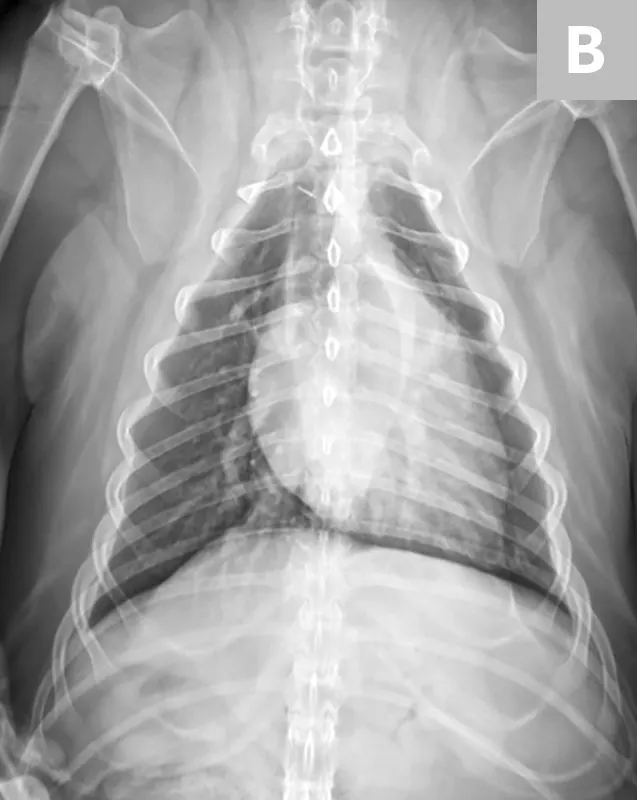

• Make sure the sternum and dorsum are superimposed on the radiograph. If the spinous processes are visible pointing to one side, move the sternum in the direction they are pointing to straighten the spine and sternum. (See Figure 5.)